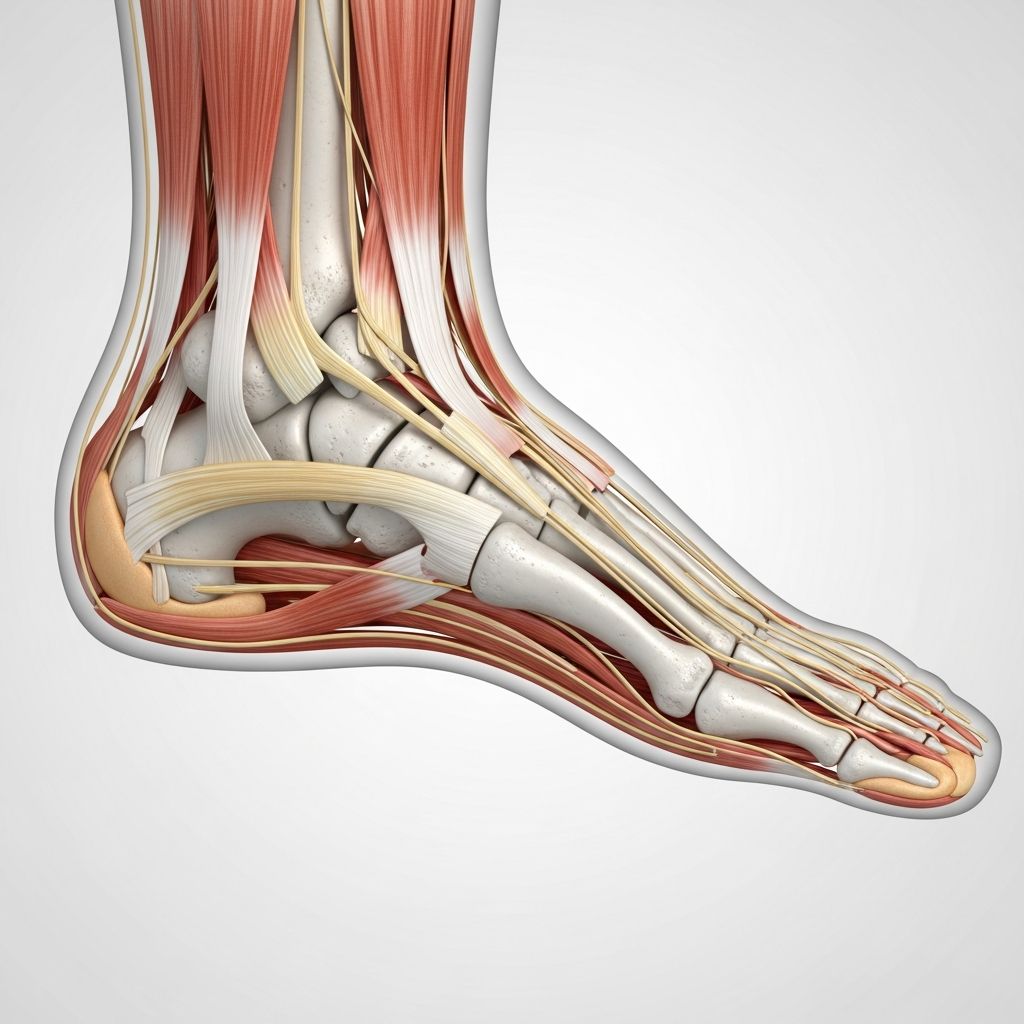

Pes cavus, commonly known as high-arched feet, is a foot condition characterized by an abnormally elevated arch along the length of the foot. Unlike a normal arch, which provides shock absorption and even weight distribution, a high arch can lead to excessive pressure on the heel and ball of the foot. This can result in discomfort, instability, and a higher risk of foot injuries.

- Neurological Disorders: Certain neurological conditions can lead to pes cavus. These include Charcot-Marie-Tooth disease, cerebral palsy, muscular dystrophy, stroke, and polio. These disorders affect the nerves and muscles, leading to muscle imbalances that result in a high arch.

- Muscular Imbalances: Imbalances in the muscles and tendons of the foot can also cause pes cavus. This can occur due to injury, trauma, or other underlying medical conditions.

- Pain: Individuals with pes cavus may experience pain, particularly in the arch, heel, or ball of the foot. This pain can be exacerbated by standing or walking for extended periods.

- Instability and Balance Issues: The elevated arch can affect balance, leading to an increased risk of ankle sprains and instability during walking or physical activities.

- Hammertoes and Claw Toes: Pes cavus can contribute to the development of hammertoes or claw toes, where the toes curl downward due to muscle imbalances.

- Physical Examination: A thorough examination of the foot will be conducted, assessing the arch height, muscle strength, and overall foot structure.

- Imaging Studies: X-rays may be ordered to visualize the bones and joints, helping determine the extent of the arch elevation and any associated deformities. In some cases, CT scans or MRIs may also be recommended.

- Orthotic Devices: Custom orthotic inserts or arch supports can help distribute weight more evenly, provide support, and alleviate pain associated with pes cavus.

- Physical Therapy: Targeted exercises focusing on stretching and strengthening specific muscles can improve foot flexibility and stability.

- Bracing: Bracing of the foot and ankle may be recommended to provide additional support and stability.

- Surgical Intervention: In severe cases or when conservative measures fail, surgical procedures may be considered to correct muscle imbalances or address structural issues contributing to pes cavus. Surgical options may include soft tissue procedures, bony surgery, and toe surgery.